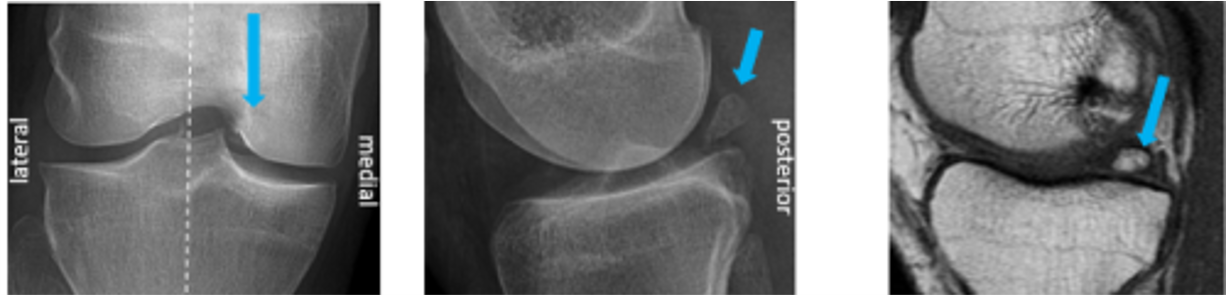

pseudodefect of the capitellum

Pseudodefect of capitellum refers to an abrupt contour change of the posterolateral margin of capitellum on coronal sections and is a potential MRI imaging pitfall giving rise to misinterpretations. It occurs because the width of the articular surface of the capitellum is non-uniform and gradually tapers posteroinferiorly.